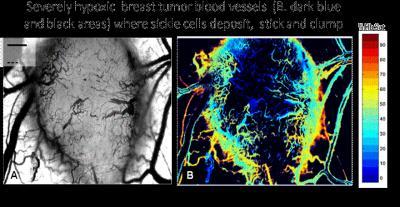

This is an intravital microscopy of the skin window of tumors in mice injected withSSRBCs or NLRBCs.

This shows severely hypoxic areas of a breast tumor (Black and dark blue on right), where sickle cells clump and bind.

(Photo Credit: Terman DS, Viglianti BL, Zennadi R, Fels D, Boruta RJ, et al. (2013) Sickle Erythrocytes Target Cytotoxics to Hypoxic Tumor Microvessels and Potentiate a Tumoricidal Response. PLoS ONE 8(1): e52543. doi:10.1371/journal.pone.0052543)